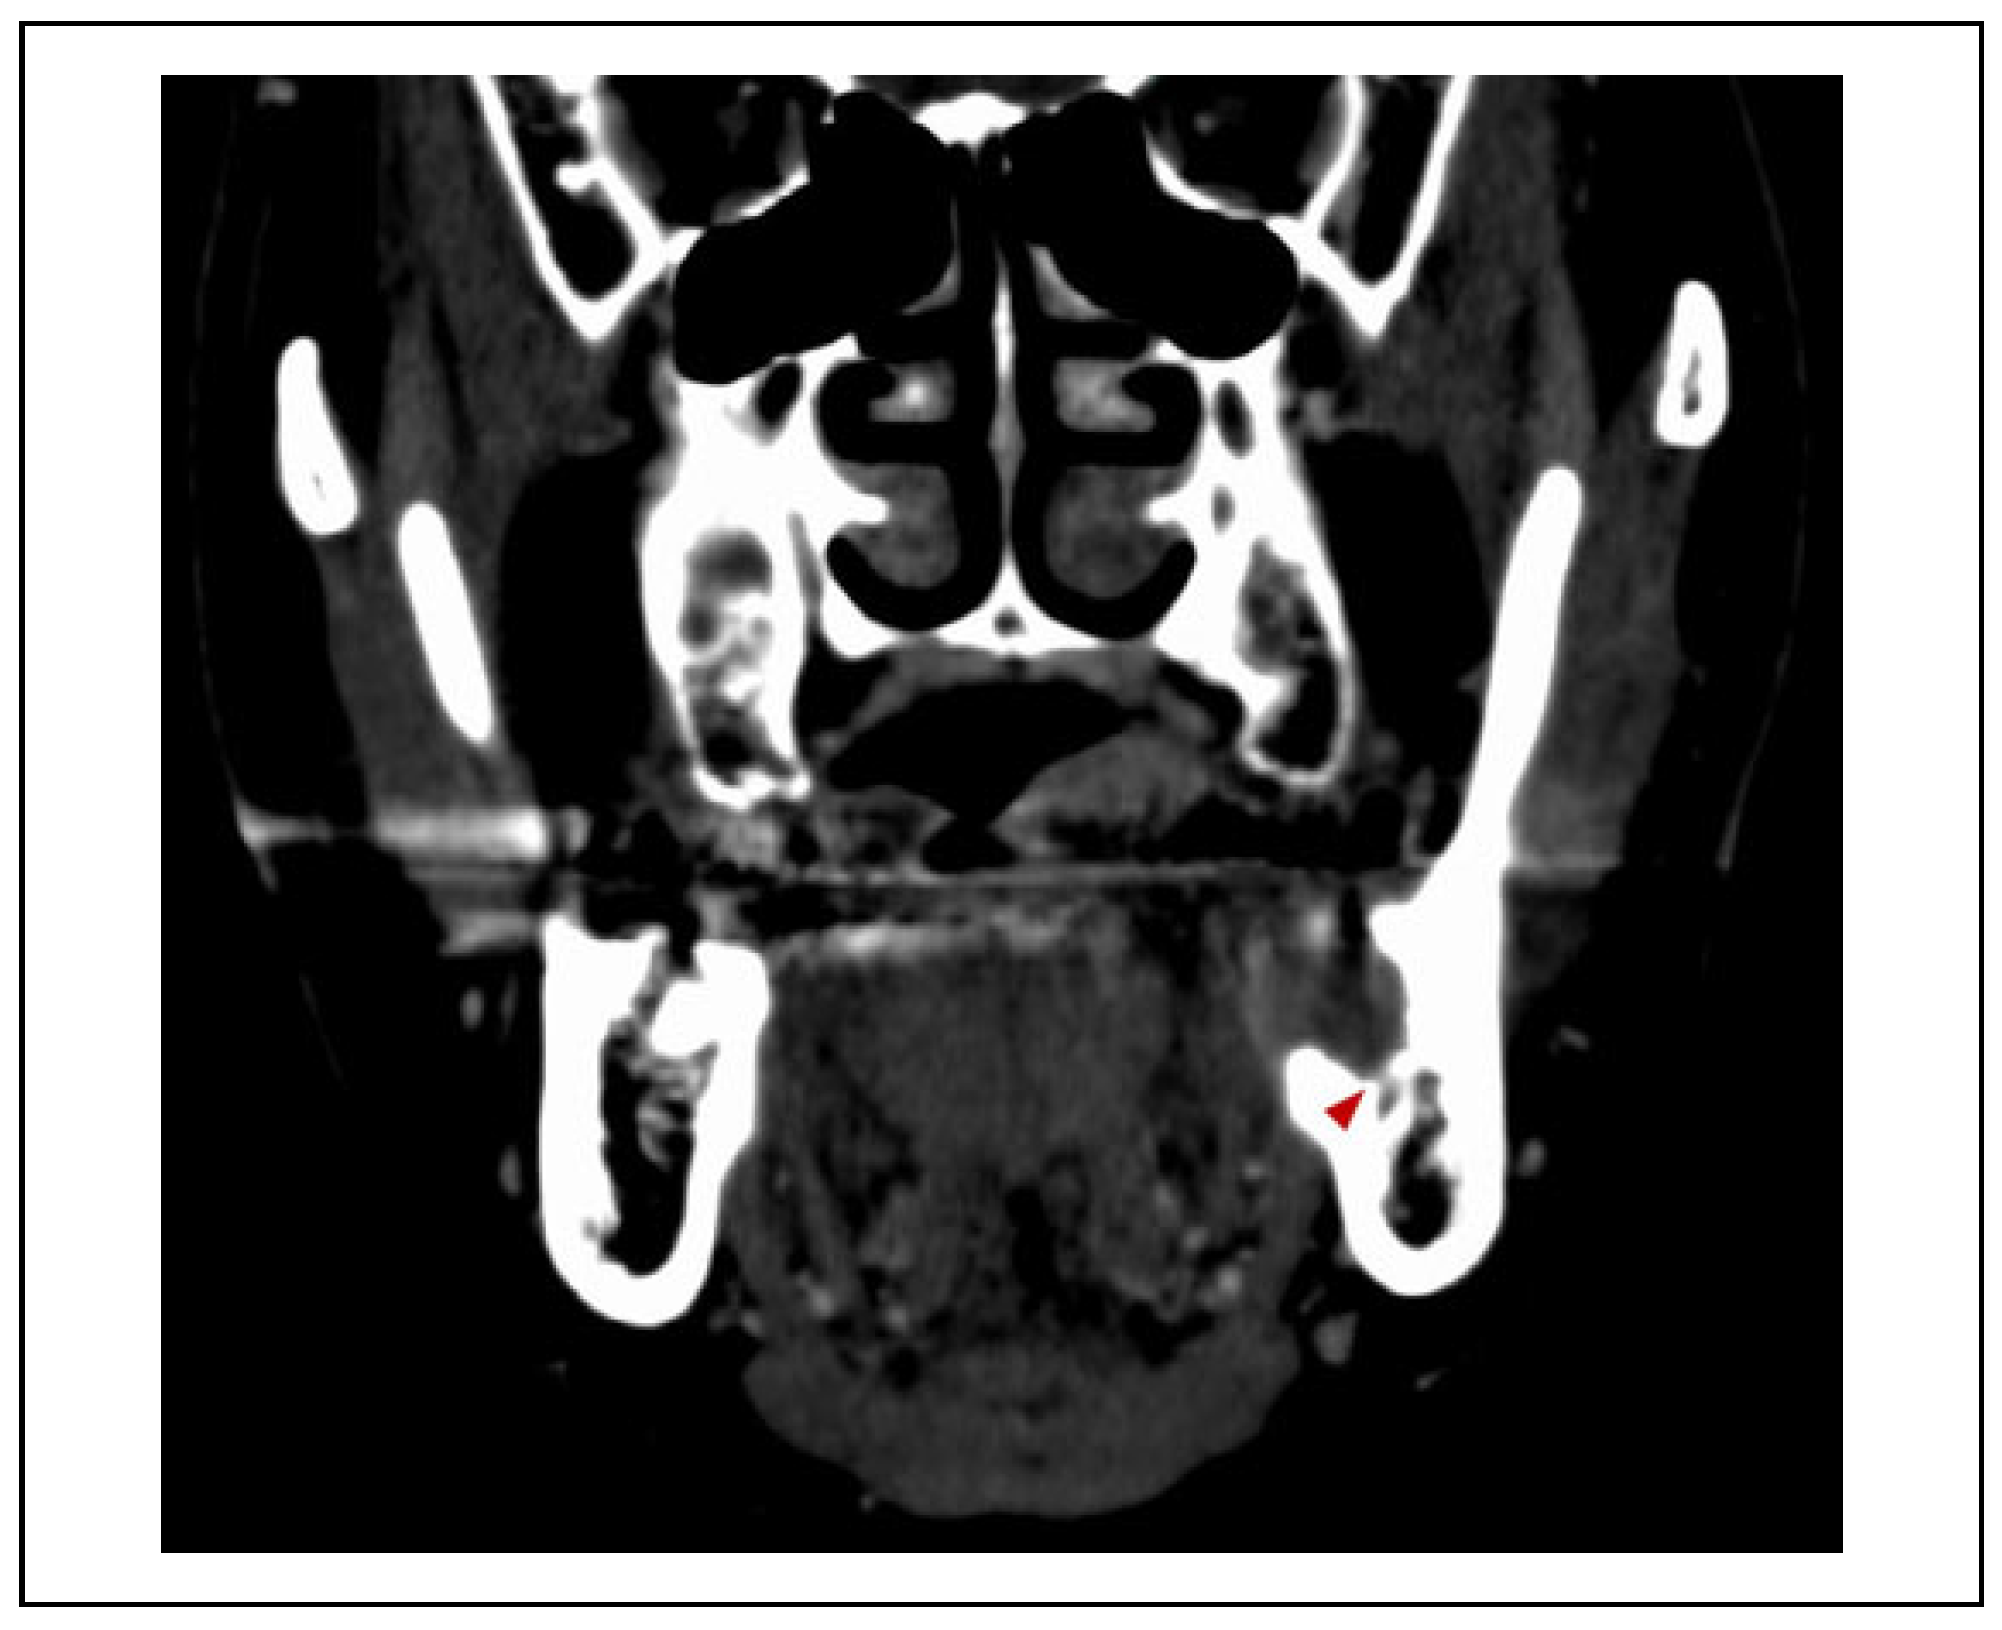

Case Presentation

Surgical Procedure